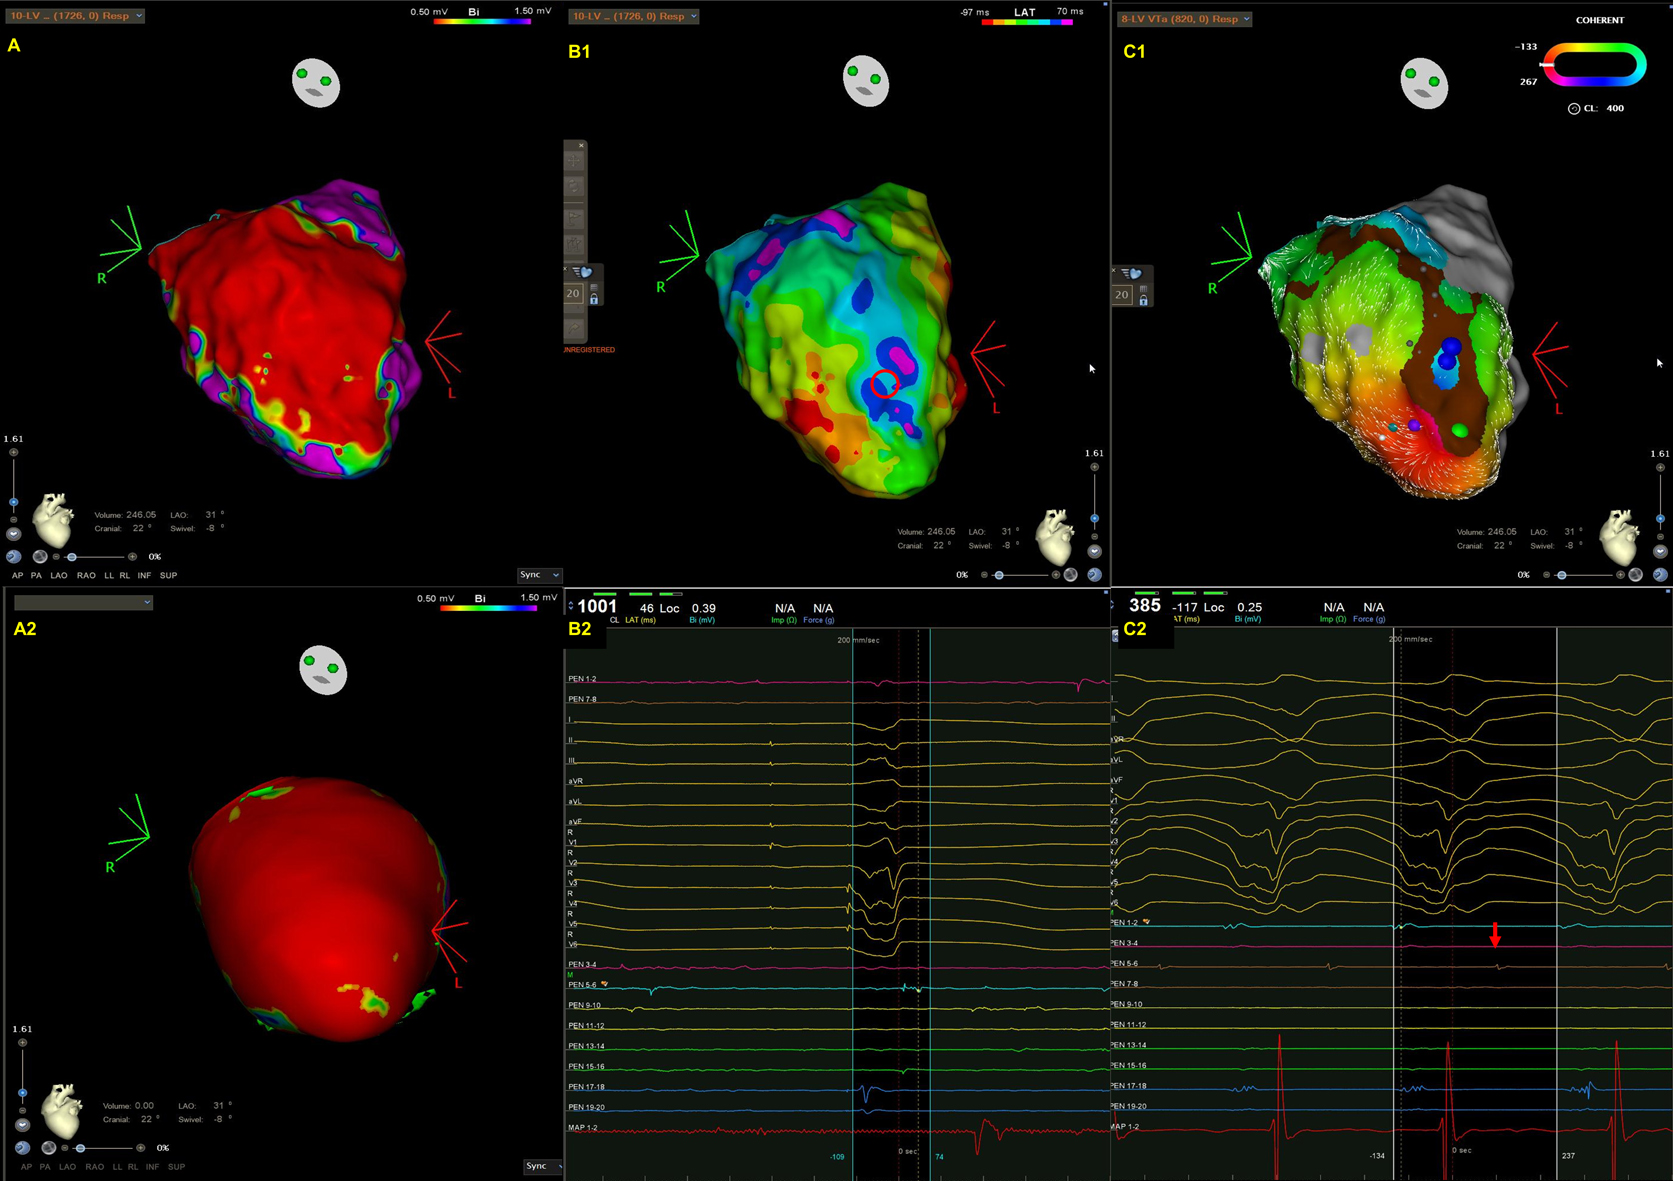

Fig. 2.A representative case of focal VT in a patient with cardiac sarcoidosis. (A) An endocardial bipolar voltage map showed extensive scarring of the LV septum and inferior wall. (B) The spontaneous VT was characterized by a left bundle branch block pattern and superior axis. Wobbling of the VT cycle lengths was also noted. (C1–2) An isochronal late activation map (C1) was created by annotating the latest component of a bipolar electrogram. At the basal inferior portion of LV, there was an isochronal crowding region. (C2) The red asterisks indicate an isolated late potential (red arrow in C1) (D1–3). VT activation map (D1), the earliest electrogram during VT mapping (D2), and pacemapping at the earliest activation site (D3). The VT activation maps (D1, from red, orange, yellow, green, blue, indigo, to violet). Contrary to the majority of scar-related VTs, there was a centrifugal pattern of activation in this patient, indicating that the mechanism of VT in this case was focal rather than macroreentrant. There was a very early prepotential (D2, green arrow) preceding the onset of VT by 128 ms in the white asterisks area (D1) where was adjacent to the isochronal crowding region. During pacemapping, the QRS morphology at the earliest activation point was 96% similar to that of clinical VT. There was also a significant delay between the stimulus and QRS onset (121 ms) during pacemapping. The VT was terminated by ablation at this site.

Cardiac sarcoidosis can affect RV, LV, or both [35, 36, 37, 38]. Patchy scarring is most often observed in the septum, followed by the anterior wall, the LV outflow tract, the inferior wall, the lateral wall, and the apex within the mid-myocardial and subepicardial layers of the LV, whereas scarring is generally seen in the RV [35, 36]. In addition, since the basal septum is frequently involved, right septal VTs, peritricuspid/perimitral VTs, or VTs originating from the Purkinje system are also common [37, 39]. A representative case was shown in Fig. 2.